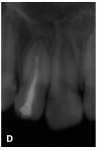

圖1B:2內(nèi)陷根管插牙膠尖片;C:2 Vitapex充填內(nèi)陷根管5個(gè)月后根尖暗影消失;

15個(gè)月后復(fù)診:X線片顯示3根尖區(qū)暗影消失,主根管牙根繼續(xù)發(fā)育,根尖孔逐漸縮?。▓D1D)。以后每隔6個(gè)月更換Vitapex 1次。

圖1D:治療后15個(gè)月2主根管牙根繼續(xù)發(fā)育,根尖孔縮??;